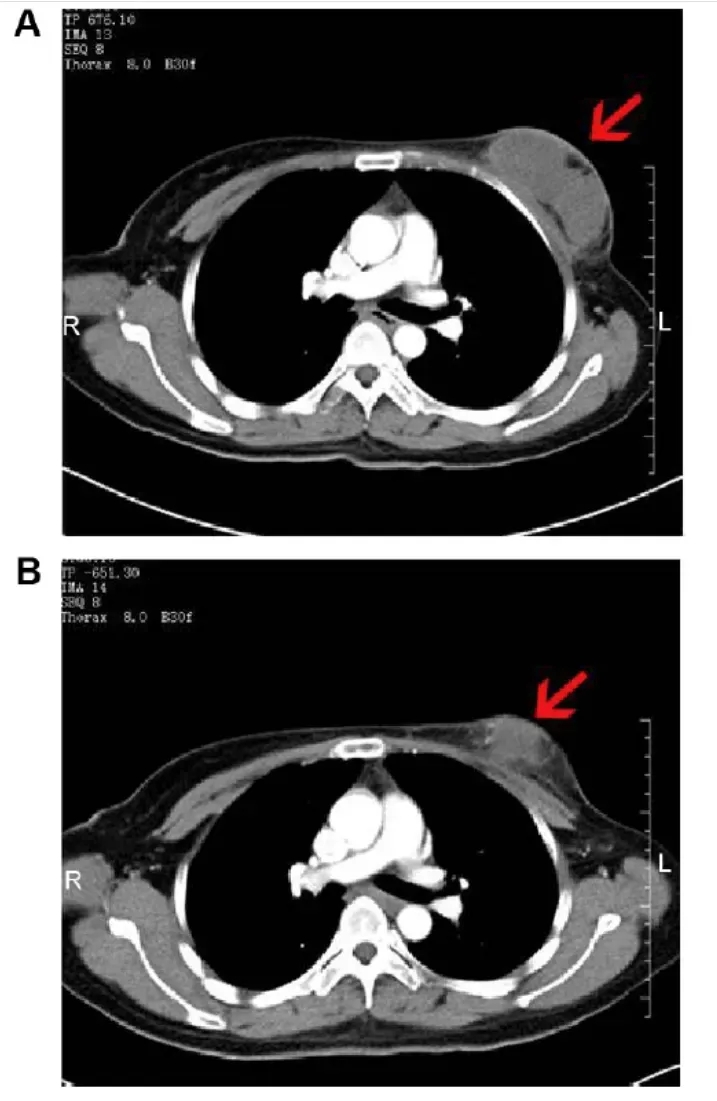

值得一提的是,一位46岁复发性乳腺癌患者的治疗效果尤为亮眼。治疗前,其右乳可见8.0×3.8×5.7cm边界不清的软组织肿块(增强CT呈中度不均匀强化),腋窝伴多处肿大淋巴结,较大者约2.9×1.7×3.8cm;接受NK细胞治疗2个月后,右乳肿块缩小至6.8×3.5×5.8cm(呈轻度不均匀强化),腋窝较大肿大淋巴结也明显缩小(详见下图)。

▲图源“Dovepress”,版权归原作者所有,如无意中侵犯了知识产权,请联系我们删除